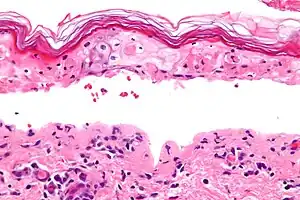

Histology

Definitive diagnosis of TEN often requires biopsy confirmation. Histologically, early TEN shows scattered necrotic keratinocytes. In more advanced TEN, full thickness epidermal necrosis is visualized, with a subepidermal split, and scant inflammatory infiltrate in the papillary dermis. Epidermal necrosis found on histology is a sensitive but nonspecific finding for TEN.[7]

Confluent Epidermal Necrosis, low mag -

Confluent Epidermal Necrosis, high mag